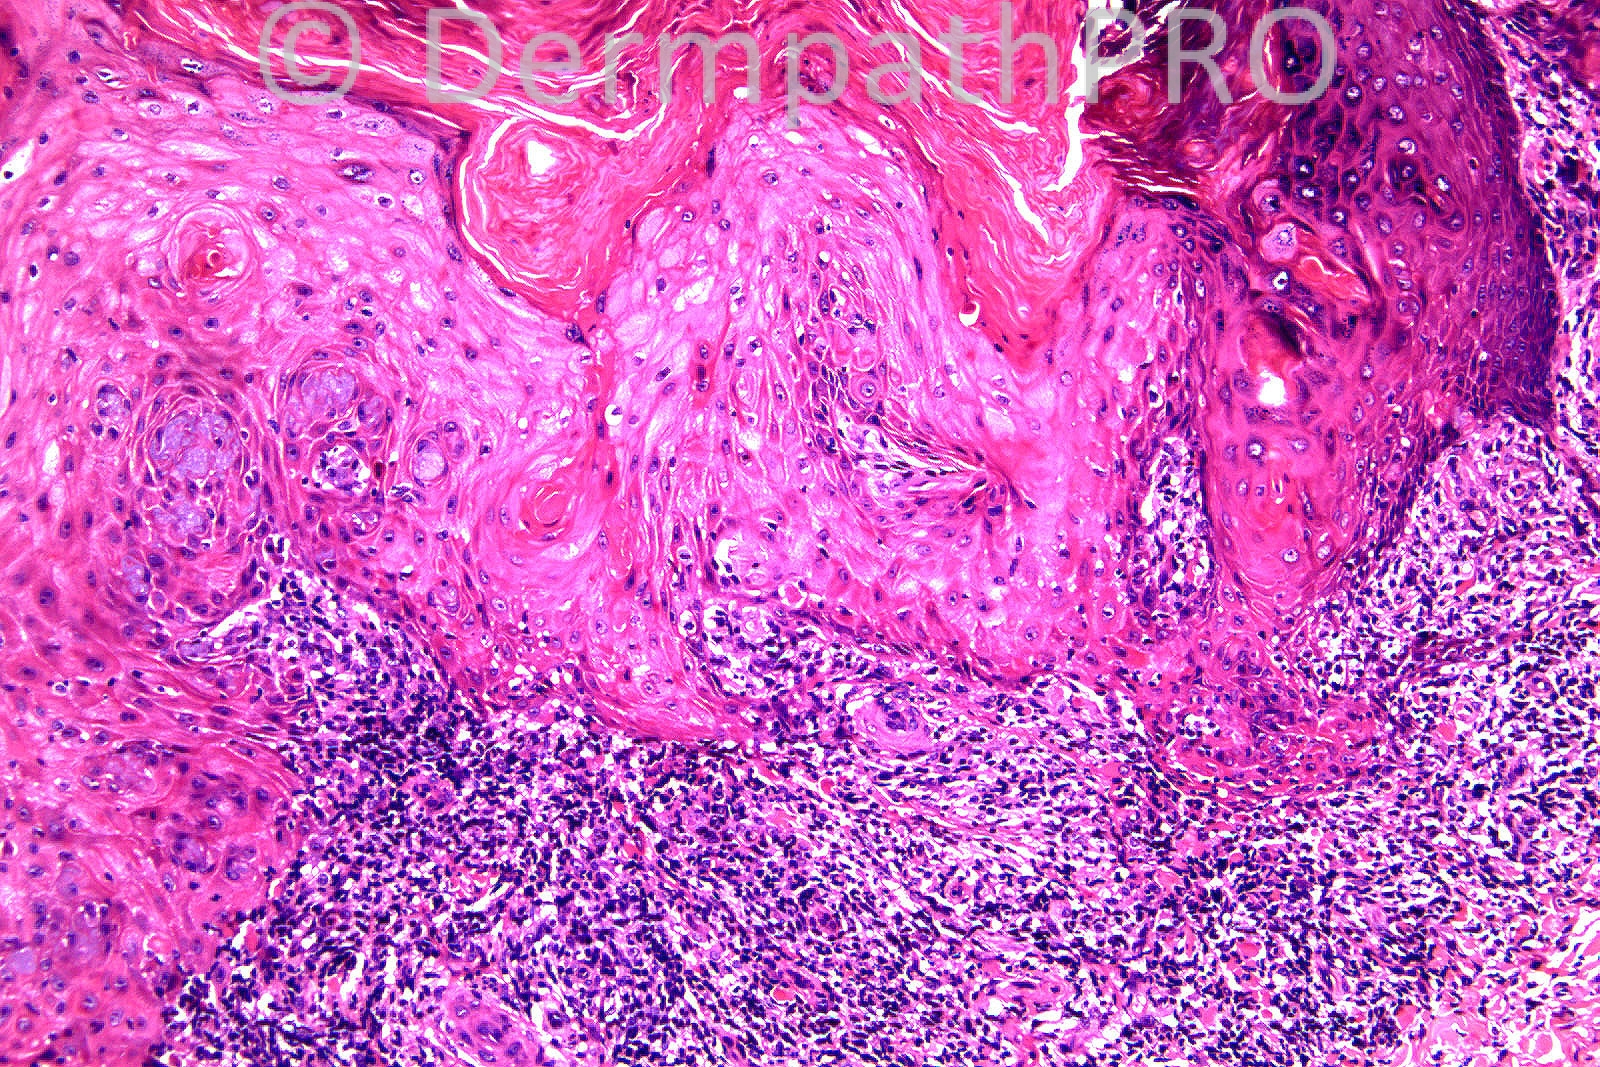

Female 70 years, arm, Nodular skin lesion L lower forearm ?BCC.